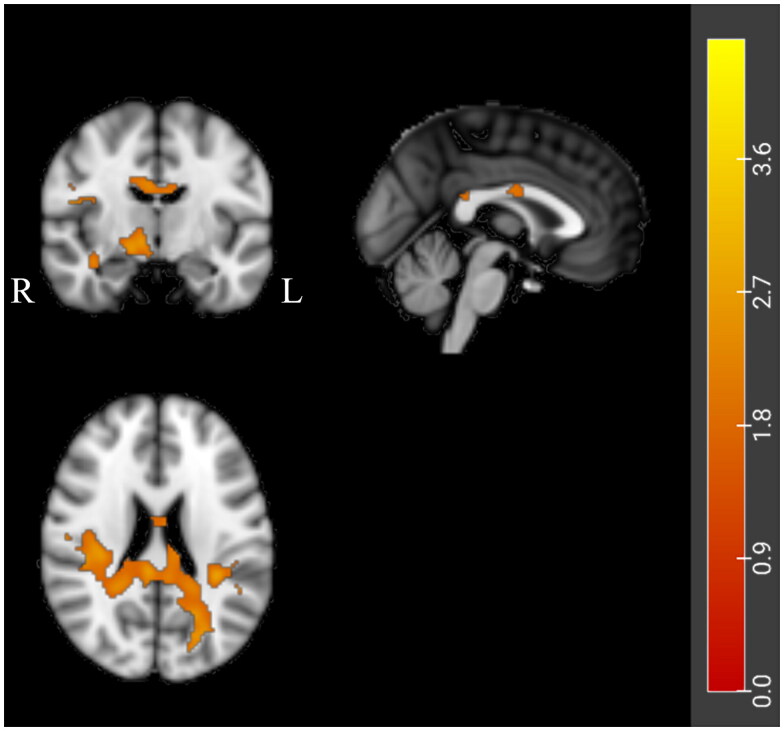

Methods: In this observational study, diffusion tensor imaging (DTI) data were acquired from 45 individuals with the upper motor neuron-dominant (UMN-D) phenotype of ALS. The UMN-D ALS patients were categorized into two groups based on the direction of symptom spread, including 25 patients with horizontal spread (group H) and 20 patients with vertical spread (group V). Diffusivity indices were derived through whole-brain analysis and probabilistic fiber tracking.

Results: According to the voxel-based analysis and tract-based spatial statistics, differences in axial diffusivity (AD) in the CC were observed between disease subgroups, with patients in group H showing higher AD values than those in group V. Fiber tracking analysis revealed persistent differences in the AD indices of CC-primary motor cortex (PMC) fibers between the two disease subgroups.